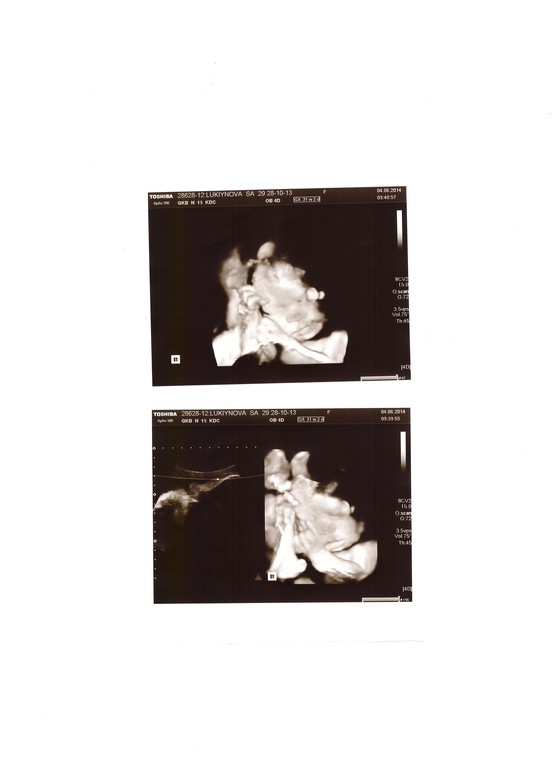

4-го июня ходила на 3-е УЗИ. Послали аж в 15 ГКБ - таааак интересно!

Меня минут 30-40 сканировали этим узи :) Показали личико малыша и даже ... его достоинство. Но, муж, ругается, говорит, что нечего на этом акцентировать внимание. А ведь так здорово!

Да, малыш опережает свой возраст - нам должна быть 32 неделя и 1 день, а он уже весит 2300 (это 33-34 недели). Это значит, что рожу раньше? Хммм... В понедельник спрошу у своего гинеколога.

Ой, чуть не забыла: малышик повернулся головой вниз, как надо! Йяху!!! Потому что за этот момент я очень переживала. Врач говорила спать на право боку. Вот теперь я могу спать как захочу и как будет удобно мальчику :)